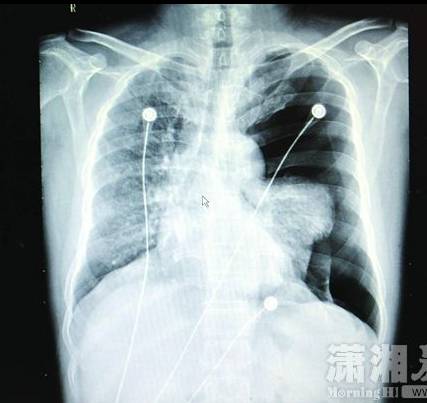

長沙汽車南站45歲男子李某K歌太猛,導(dǎo)致肺大皰破裂引發(fā)了氣胸,被家人緊急送到醫(yī)院搶救。1月14日,瀟湘晨報(bào)記者從長沙市中心醫(yī)院獲悉,經(jīng)開胸手術(shù)后李某才保住性命。

"患者入院時(shí)呼吸、講話很困難,不能平臥,左手緊緊捂著胸口,有明顯的呼吸困難、胸痛等癥狀。緊急檢查發(fā)現(xiàn),其左側(cè)重度氣胸,左肺已壓縮60%以上,心臟受壓移位;若不及時(shí)處理,很可能危及生命。"長沙市中心醫(yī)院胸心外科副主任醫(yī)師彭建明介紹,人的胸膜腔是密閉的、不含空氣的潛在性腔隙,在一些先天因素的影響下,有部分小肺泡會逐漸融合成一個(gè)巨大的、沒有氣體交換功能的肺大皰,導(dǎo)致肺組織彈性下降;當(dāng)劇烈咳嗽、踢足球、提重物、大笑、K歌等用力過猛活動(dòng)時(shí),肺內(nèi)壓力突然增加,很可能導(dǎo)致肺大皰破裂發(fā)生氣胸,氣體進(jìn)入胸膜腔導(dǎo)致肺葉被壓縮,從而引起呼吸困難,嚴(yán)重時(shí)可危及生命。彭建明說:"醫(yī)生在全麻胸腔鏡下為李先生行微創(chuàng)手術(shù),術(shù)后恢復(fù)情況良好,順利出院。"